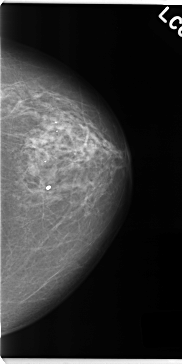

C_0128_1.LEFT_CC

LEFT_CC LINES 4720 PIXELS_PER_LINE 2360 BITS_PER_PIXEL 12 RESOLUTION 50 NON_OVERLAY